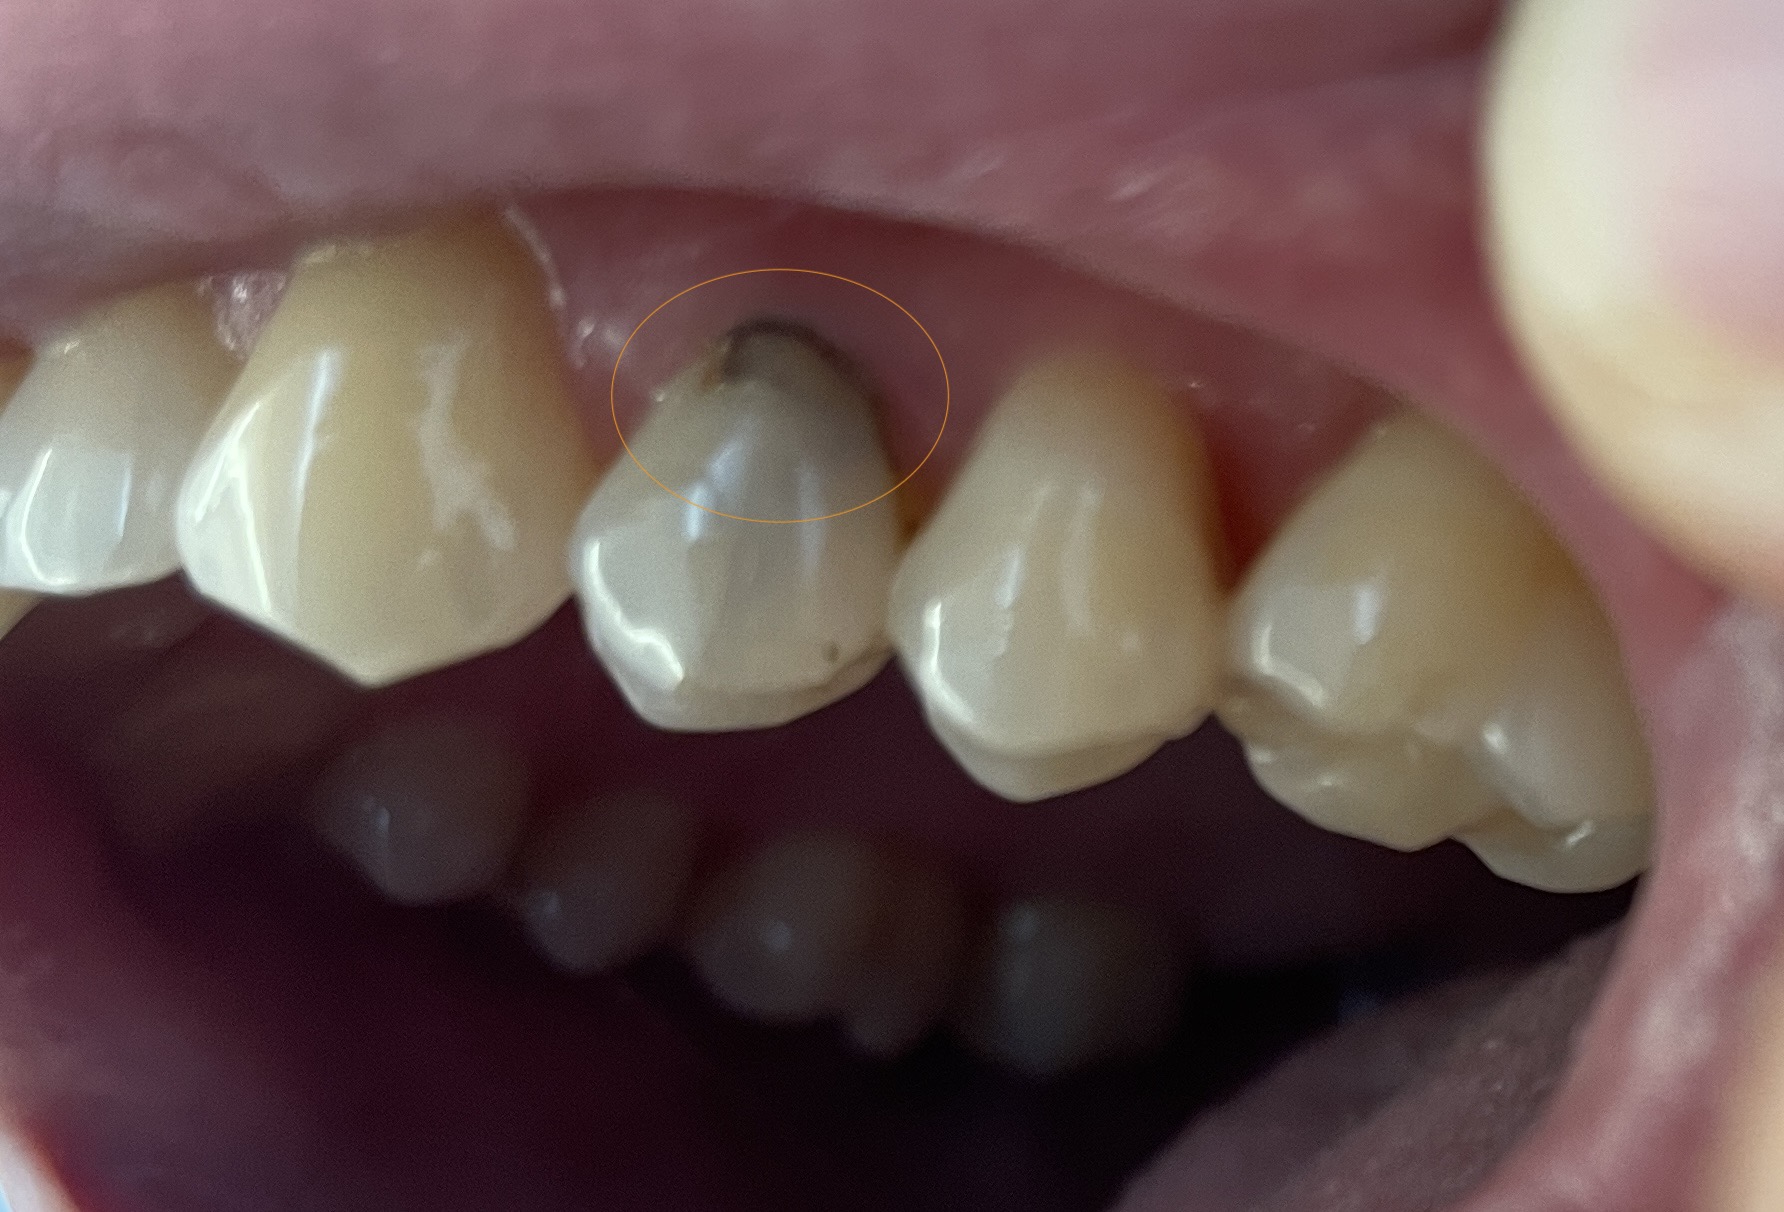

Ik ben er niet zeker van dat twee (x2) V93 Drievlaksvulling composiet geschikt is voor de kleine tandverkleuring die ik heb. Wat denk je? Kan het zijn dat mijn tandarts mij te veel in rekening probeert te brengen omdat ik verzekerd ben? De foto is bijgevoegd.

Ik zie nu alleen de buitenkant. Vervanging v d bestaande vulling zal , op foto te beoordelen maar geen x-foto gezien of er meer aan de hand is, mi geen 3 vl vulling zijn maar eerder een 1 vl.. Ik begroot altijd meer dan in werkelijkheid zodat ik achteraf geen gezeur krijg als het meer wordt. Maar als het minder is reken ik ook minder. Als ik te weinig begroot en het wordt meer dan is het hek v d dam. Weet u zeker dat er geen tweede vulling nodig is. Bespreek het vooraf met uw tandarts. Zou de x-foto moeten zien. Blokkeer de namen en post hier de begroting.

Rekening gezien, maar voor de mee lezers hier niet zichtbaar, dus niet duidelijk. Denk nit dat ik twee drievlaks zou begroten. Maar heb dus niet volledig beeld.

Hartelijk dank voor uw antwoord, het is zeer nuttig! Ja, ik begrijp dat je de prijs iets moet verhogen en vervolgens verlagen als dat nodig is. Het klinkt eerlijk en betrouwbaar. Toch vertelde mijn tandarts mij dat de x-foto goed is, dat de uiterst linker tand met gevulde wortel vanbinnen geen problemen heeft, en dat de behandeling zelf nu niet eens nodig is. Hij vertelde mij dat hij mij de rekening zou sturen als ik deze verkleuring, die je ziet op de foto die ik heb gemaakt, wil laten behandelen.

ik vermoed dat de aanwezige vulling zeg maar bovenop ook vervangen wordt, vanwege de toch diepere verkleuring. Maar er is maar 1 manier om erachter te komen: even toelichting vragen.